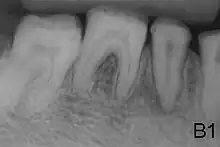

- Type 2 - Hypomaturation

- Enamel has sound thickness, with a pitted appearance. It is less hard compared to normal enamel, and are prone to rapid wear, although not as intense as Type 3 AI. Condition is of autosomal dominant, autosomal recessive, or x-linked pattern. Enamel appears to be comparable to dentine in its radiodensity on radiographs.